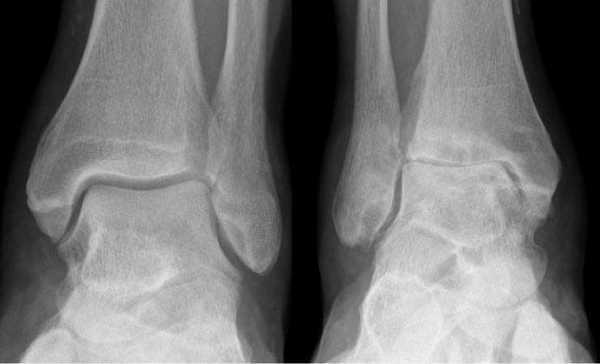

Рис. 1. Рентгенограммы пациента К. в опоре при поступлении: асептический некроз блока таранной кости, дефект малоберцовой кости, эквино-вальгусная деформация левой стопы

После проведенного клинико-рентгенологического исследования пациенту был поставлен диагноз: Приобретенная посттравматическая деформация левого голеностопного сустава как следствие асептического некроза блока таранной кости. Несостоявшийся анкилоз левого голеностопного сустава. Не опорная левая стопа. Синдром крузалгии, тарзалгии слева (рис. 1).